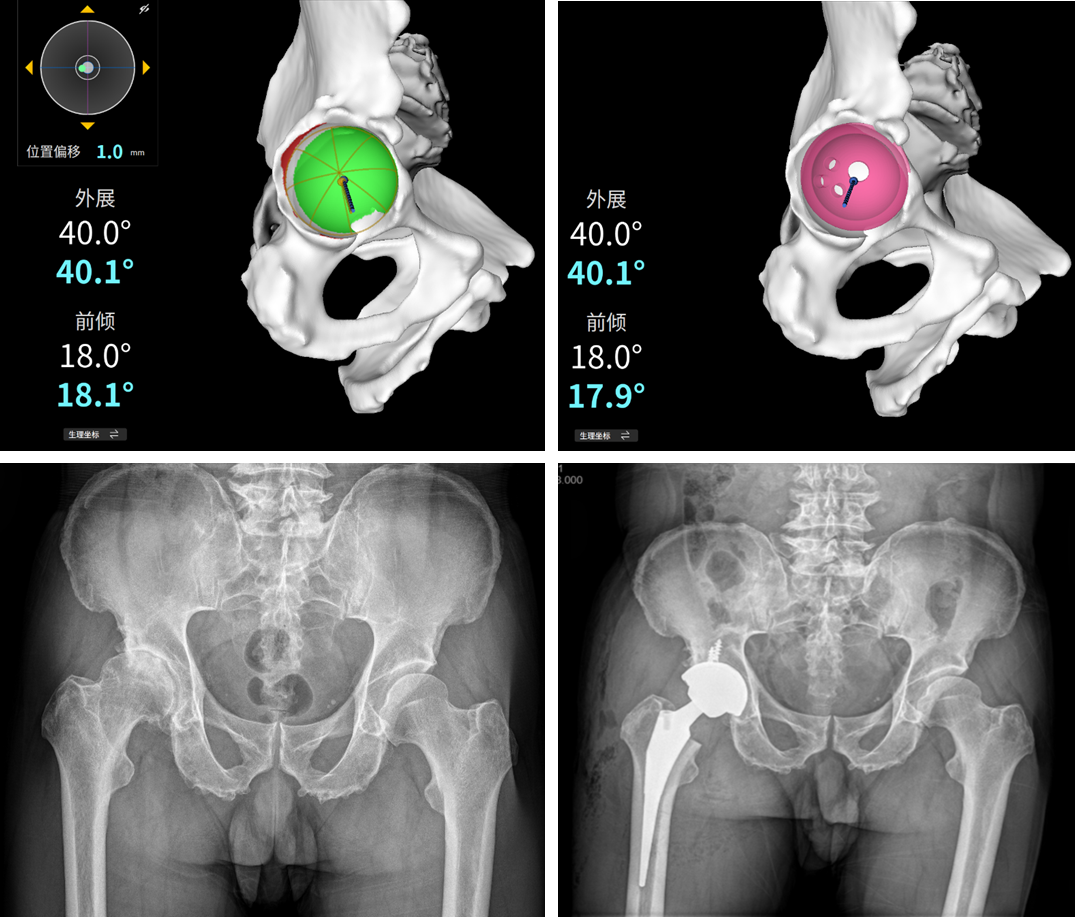

首台机器人辅助髋关节置换手术

现年69岁的Y先生,因右侧髋关节疼痛2年、加重1月,慕名来到浙江大学医学院附属邵逸夫医院就诊,经验丰富的施培华教授确诊患者患有右侧股骨头坏死合并髋关节骨性关节炎,需行全髋关节置换手术。骨科团队经过讨论和详细研判,认为传统手术风险较高,决定采用医院新引进的国产智能关节机器人ARTHROBOT辅助手术,以确保手术的精准性和安全性。

术前通过详细的患者CT扫描数据分析,根据Y先生的骨骼形态、解剖标志等个体特征,依托关节机器人智能手术规划系统,对假体型号、安装位置和角度、双下肢长度、联合偏心距等数据进行了亚毫米级别的精准测量和设计。术中,ARTHROBOT展现了其可视化、数字化、精准化的手术操作优势,10s内实现髋臼“一锉到底”,3分钟内完成髋臼杯和股骨假体的精准安放,术后评估臼杯位置误差在1度以内,双下肢等长,即刻髋关节屈伸活动自如,关节稳定,在高度屈曲和内旋情况下均无脱位风险。患者及其家属对手术效果非常满意。